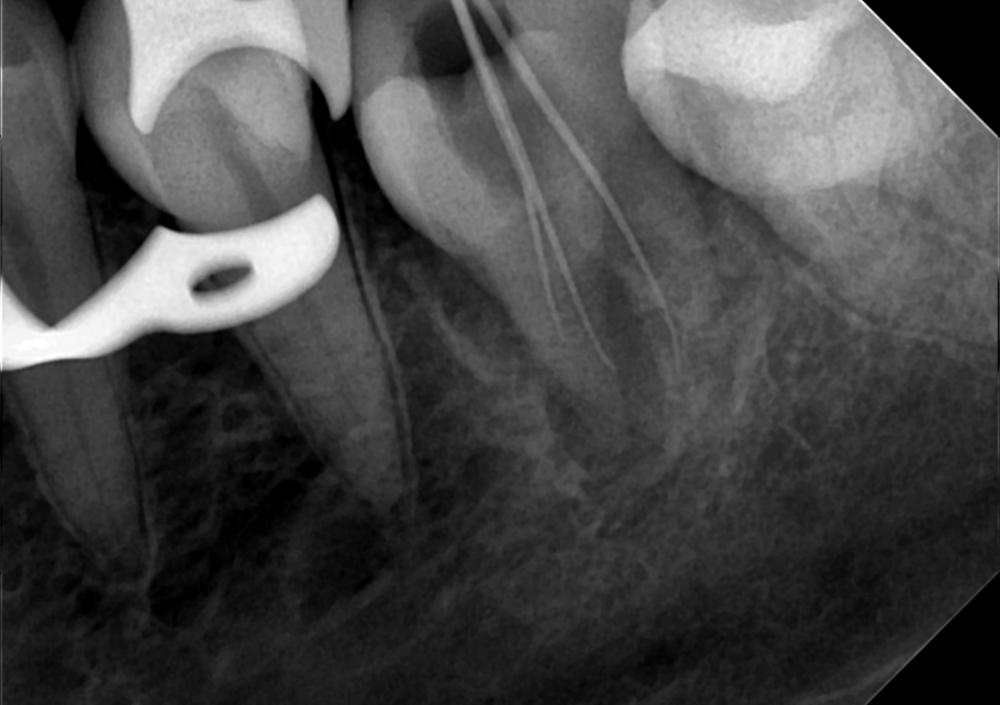

Dr.Deletle Опубликовано 22 июля, 2023 Поделиться Опубликовано 22 июля, 2023 (изменено) Этот кейс интересен тем, что у пересаживаемого 2.8 полностью сформированы корни. Пациент Н., 35лет, зуб 3.6 подлежит удалению по терапевтическим показаниям. Донором был выбран зуб 2.8. Фото №1, 2 - ситуация ДО на фото и срезе КЛКТ Фото №3 - планирование на реконструкции ОПТГ из КЛКТ Фото №4 - шаблон зуба 2.8 Фото №5, 6 - операция, удален 3.6, припасован шаблон, пересажен 2.8 (фиксирован швами и шиной к 3.7) Фото №7 - КТ сразу после пересадки Фото №8, 9 - депульпирование пересаженного 2.8 через 2 недели Фото №10 - снятие шины через 2нед после пересадки Фото № 11, 12, 13 - состояние в полости рта и на срезе КТ через год после пересадки, видно сформированное периодонтальное пространство, здоровая костная ткань, жалоб у пациента нет, полноценно жует как обычным зубом Изменено 22 июля, 2023 пользователем Dr.Deletle 4 3 Ссылка на комментарий

АнтонТЛТ Опубликовано 23 июля, 2023 Поделиться Опубликовано 23 июля, 2023 По этому кт выглядит так, что будто каналы не до конца запломбированы и нет апроксимальных контактов. Ссылка на комментарий